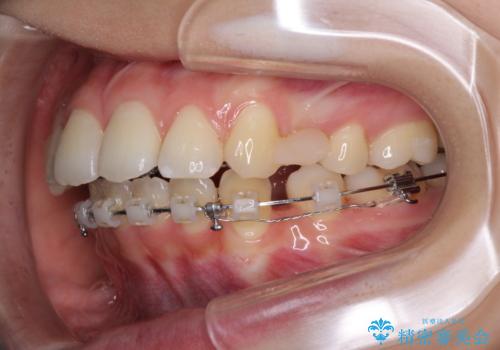

- ハーフリンガル

目立たない装置が希望であったため、上顎が裏側装置である、ハーフリンガル装置を選択されました。

3年半ほどで終わる予定でしたが、途中引っ越し、出産、引っ越し、出産を繰り返し、なかなか来院することができず、装置を外すまでに8年以上の期間がかかってしまいました。